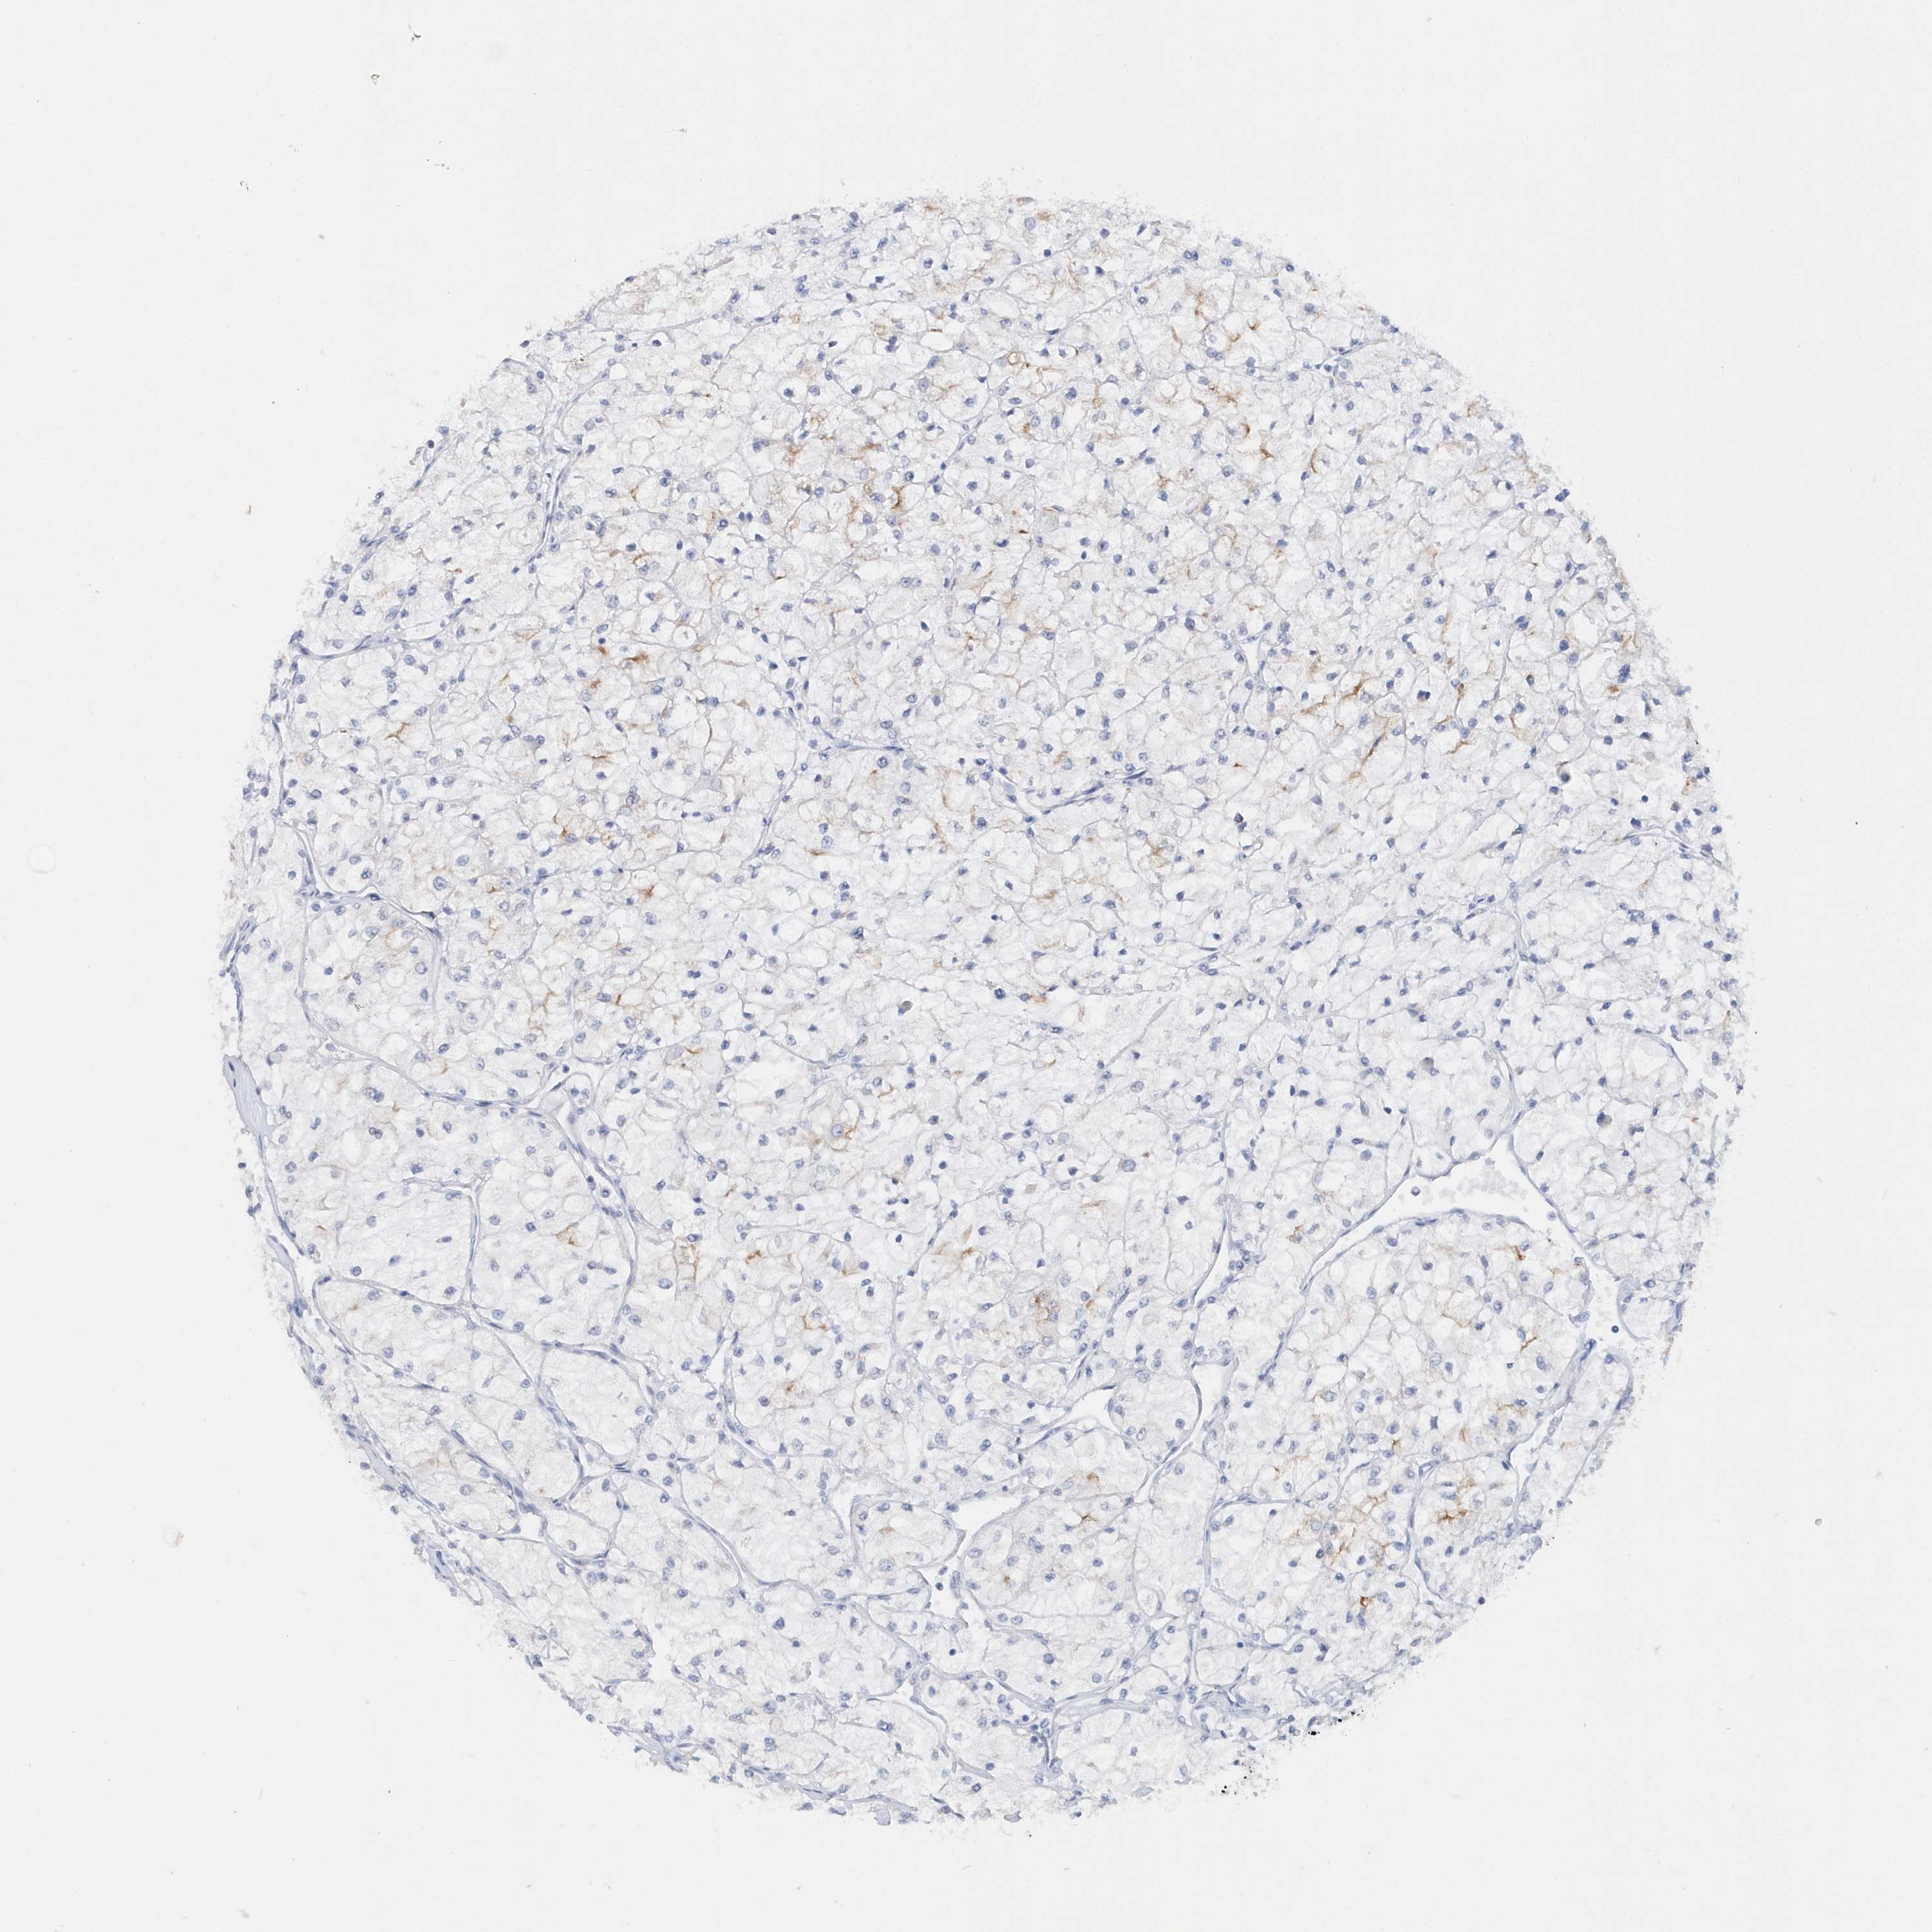

TCGA-UZ-A9PO-01A 80 years, male, white, stage:Stage I, alive, 1911 days 22.4

TCGA-MH-A561-01A 66 years, male, white, stage:Stage I, alive, 841 days 22.4

TCGA-SX-A7SN-01A 52 years, male, white, stage:Stage I, alive, 578 days 22.1

TCGA-SX-A71W-01A 66 years, male, white, stage:Stage I, alive, 1076 days 22.1

TCGA-DW-7836-01A 55 years, male, white, stage:Stage I, alive, 1093 days 22.0

TCGA-BQ-5885-01A 63 years, male, white, stage:Stage III, alive, 921 days 22.0

TCGA-4A-A93W-01A 66 years, female, white, stage:Stage I, alive, 4 days 21.8

TCGA-GL-A59T-01A 46 years, male, white, stage:Stage I, alive, 546 days 21.7